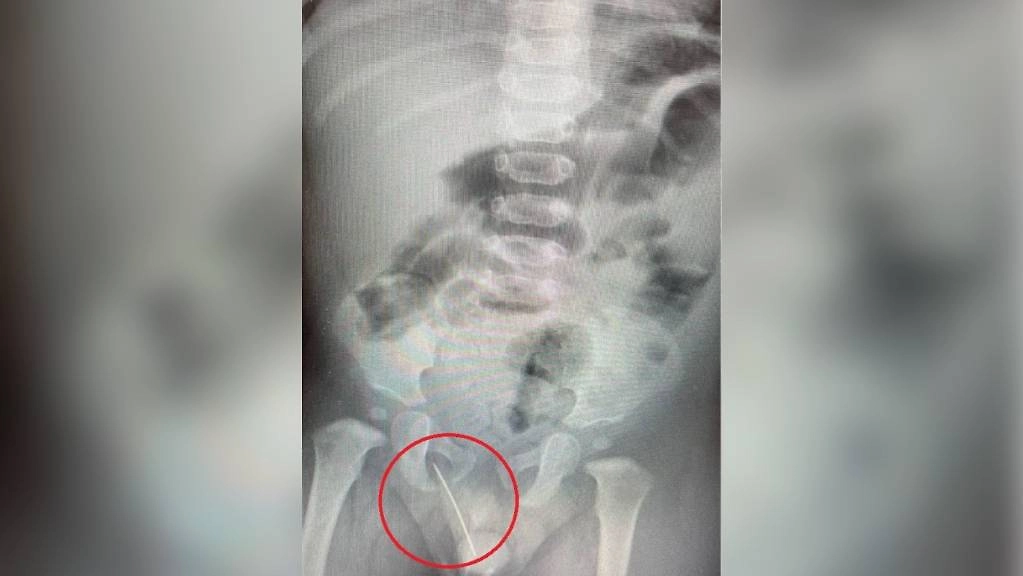

Иголка, застрявшая в теле малыша. Фото © Министерство здравоохранения по Московской области

«Инородным телом стала швейная игла, которая прошла в опасной близости от уретры. Вероятнее всего, мальчик случайно сел на неё. Мы выполнили ребёнку экстренную операцию по извлечению инородного тела, после которой болевой синдром был полностью купирован. Операция прошла успешно, без осложнений», — сказал заведующий отделением детской хирургии №1 Евгений Рожденкин.